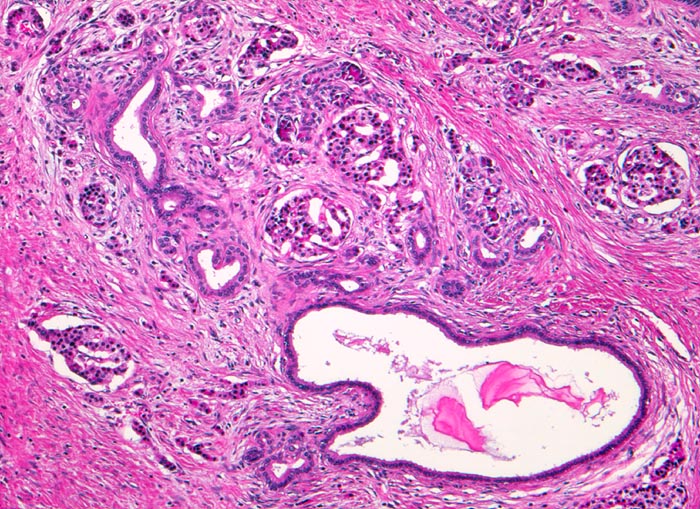

Je nach Ursache der chronischen Pankreatitis unterscheidet sich das Muster der Fibrose. Die Nekrosen des interlobulären Gewebes und der interlobulären Gänge bei ethylischen Pankreatitisschüben führen primär zu einer interlobulären Fibrose und interlobulären Gangstrikturen. In den betroffenen interlobulären Gängen führt der Sekretstau zur Konkrementbildung (verkalkte Proteinpräzipitate). Wie bei einer chronisch obstruktiven Pankreatitis kommt es in den unvollständig drainierten Läppchen zu einer Atrophie der Azini verbunden mit intralobulärer Fibrose. Letztere Areale enthalten schliesslich nur noch Reste unregelmässig verteilter Gänge, Inseln, Nerven und Gefässe. In vielen Fällen lassen sich extrapankreatische Pseudozysten gefüllt mit nekrotisch-hämorrhagischem Detritus in der Nachbarschaft der fibrosierten Bezirke nachweisen. Ein Tumor (> 2066), eine Narbe oder einen Stein können als Folge einer Obstruktion des Pankreasganges im Pankreaskopf eine diffuse Atrophie und Fibrose des Pankreas nach sich ziehen. Diese Form wird als chronische obstruktive Pankreatitis bezeichnet und ist gekennzeichnet durch eine deutliche poststenotische Dilatation des betroffenen Pankreasganges ohne Konkrementbildung und eine diffuse Fibrose des an den obstruierten Gang angrenzenden Parenchyms. Bei einer Schädigung des Gangepithels und der Gangwände wie bei hereditärer oder Autoimmunpankreatitis entwickelt sich primär eine periduktale Fibrose. Im Gegensatz zum duktalen Adenokarzinom ist das erhaltene Parenchym bei der chronischen Pankreatitis lobulär angeordnet. Drüsenepithelien zeigen keine Atypien. Karzinomverdächtig sind irregulär infiltrierende atypische Drüsen, atypische Drüsen in unmittelbarer Nachbarschaft von grösseren Gefässen ohne dazwischenliegende Azini, Perineuralscheideninvasion, rupturierte oder inkomplette Drüsen, und Drüsen mit luminalem nekrotischem Detritus.

• Erhaltene Läppchenarchitektur.

• Breite Bänder von sklerosiertem zellarmem Bindegewebe verlaufen zwischen den Läppchen.

• Atrophie des exokrinen Pankreas.

• Erhaltene Inseln und Gangstrukturen.

• Spärliches chronisches Entzündungsinfiltrat.